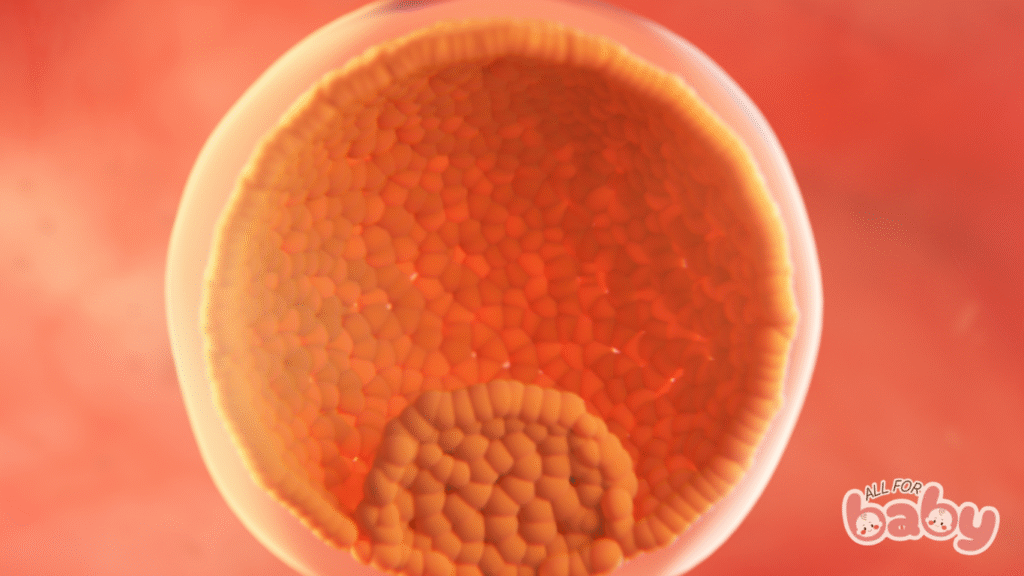

Ở tuần 4, bé chính thức được gọi là phôi thai (embryo).

Phôi lúc này được tạo thành từ 2 lớp tế bào chính:

Lớp nội bì (endoderm): Sẽ phát triển thành phổi, gan, hệ tiêu hóa.

Lớp ngoại bì (ectoderm): Sẽ hình thành não, hệ thần kinh, da và tóc.

Nhau thai nguyên thủy cũng đang phát triển, chuẩn bị đảm nhận vai trò vận chuyển oxy và dưỡng chất từ mẹ sang bé trong những tuần tiếp theo.